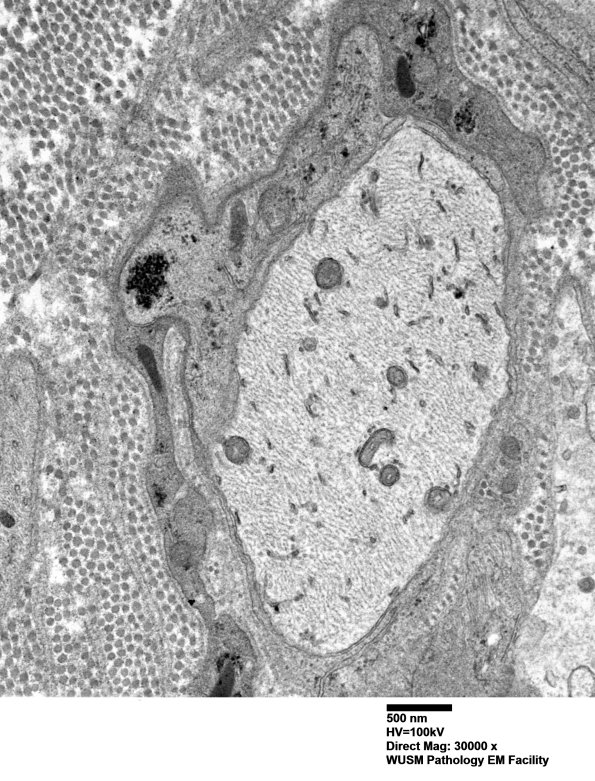

Washington University Experience | PERIPHERAL NEUROPATHY | 6 AXONAL DEMYELINATION (BASIC PROCESS) | 5B8 (Case 5) EM 022 - Copy

Higher magnification of image #5B7. (electron micrograph)